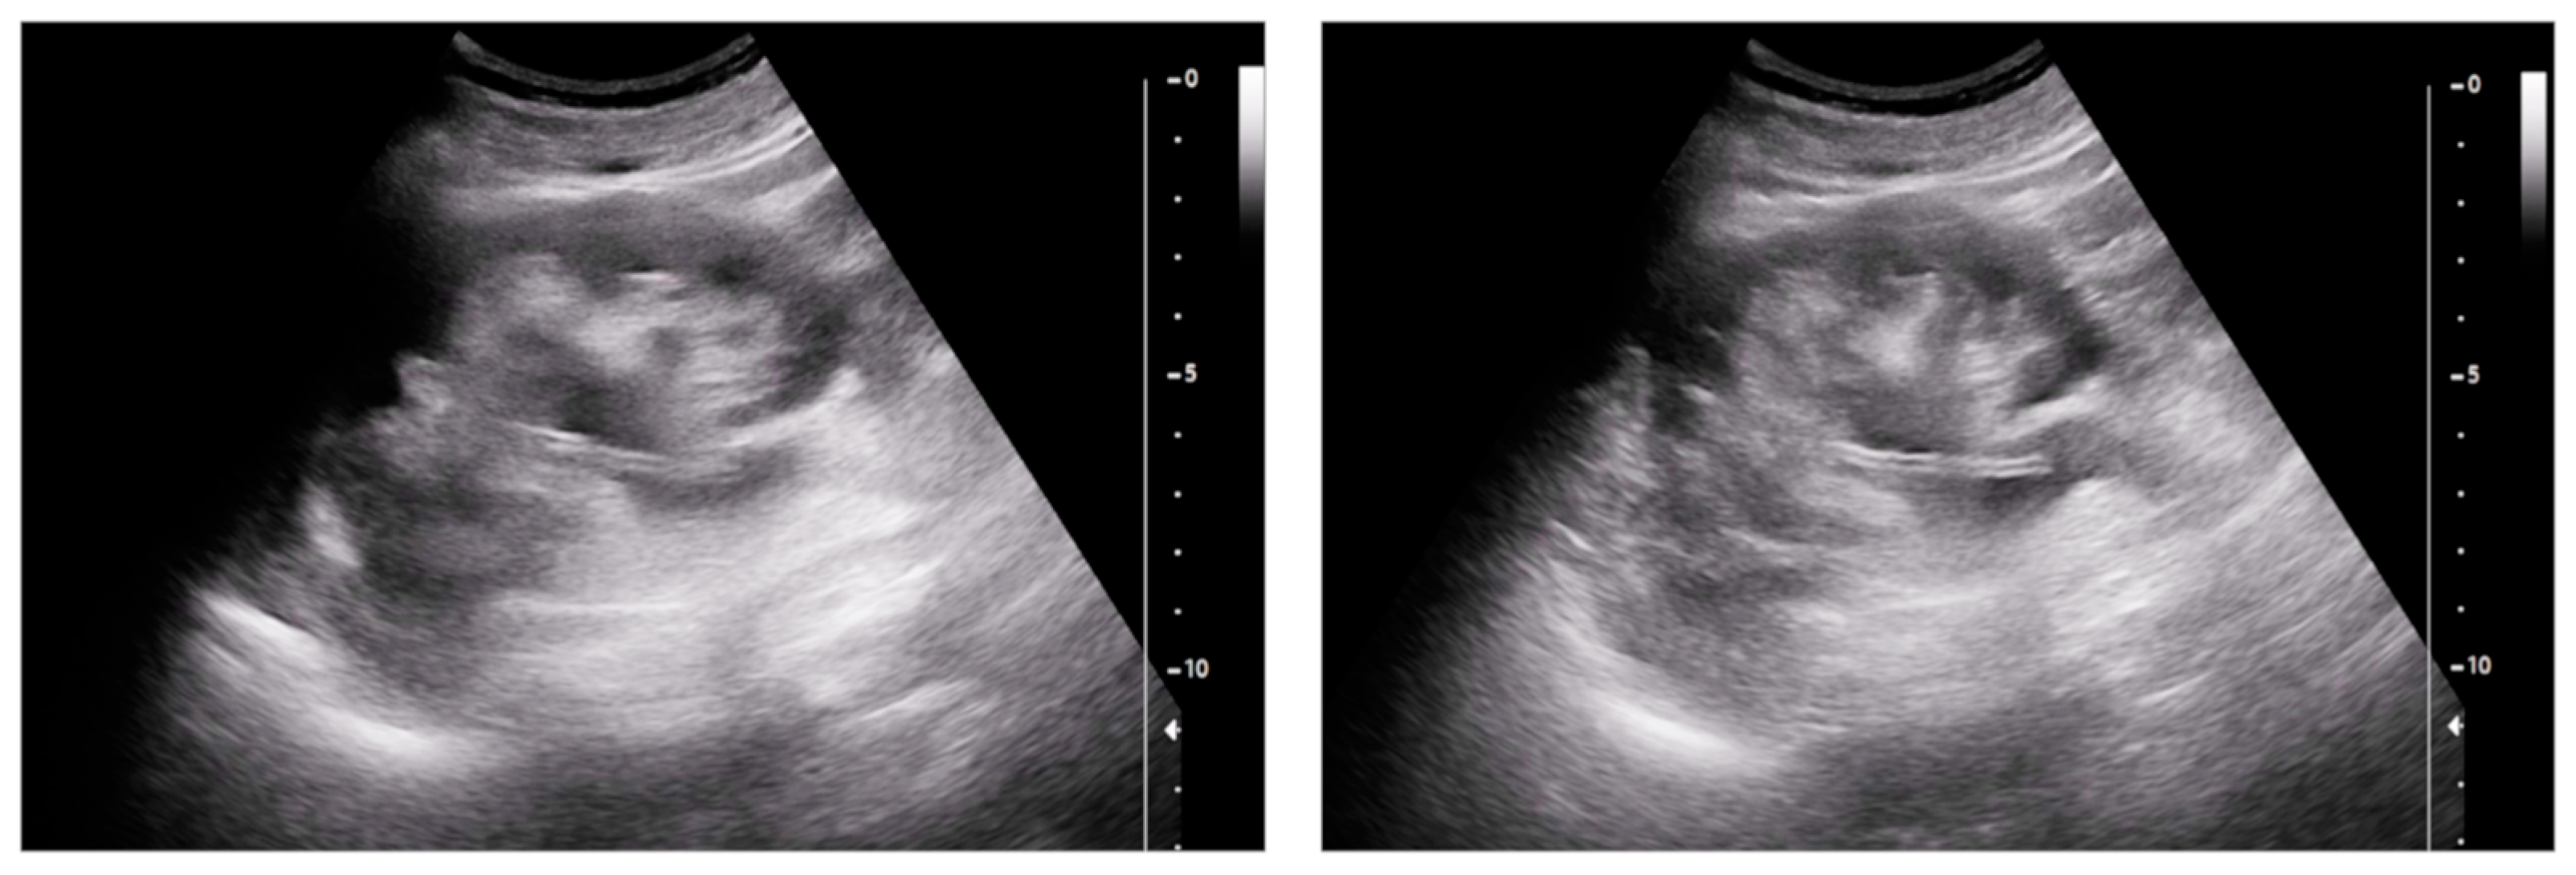

- Urinary tract infection: Stent colonization by bacteria, with an overall incidence ranging from 42% to 90%, is a significant clinical challenge that can lead to a urinary tract infection. In some instances, this infection can result in complications, such as acute pyelonephritis (Figure 8) and renal failure [31,32]. For most patients experiencing a ureteral obstruction, stent placement is carried out with antibiotic prophylaxis, typically administered as a single dose concurrent with the procedure. In cases where a urinary tract infection is already known, the insertion of the stent should be delayed whenever possible until the appropriate treatment with culture-specific antibiotics allows for urine sterilization [32]. US serves as the first-line diagnostic tool to assess the urinary tract in patients presenting with the symptoms of pyelonephritis. Unfortunately, pyelonephritis lacks clear gray-scale findings useful during characterization [33]. Consequently, most patients with clinically suspected pyelonephritis have negative results from US. In cases where imaging is deemed necessary, CT emerges as the preferred modality, providing comprehensive anatomical and physiological information and accurately delineating both intra- and extra-renal pathological conditions. The presence of urinary tract gas, calculi, hemorrhage, renal enlargement, inflammatory masses, and obstruction can be easily detected by CT. Specifically, the affected regions may show a lower attenuation due to edema with pockets of higher attenuation representing the foci of hemorrhage. However, these findings are frequently absent, and unenhanced CT images may appear normal. It is only after the administration of contrast material that the diagnostic features of pyelonephritis become evident. In advanced stages, sepsis is a potential complication, occasionally presenting a critical issue in a debilitated cancer patient. The close monitoring of the patients after the procedure is imperative, with a heightened awareness of the potential for sepsis. The incidence of sepsis following catheter insertion varies between 1.5% and 7%, particularly in patients with pyelonephritis [1,2].